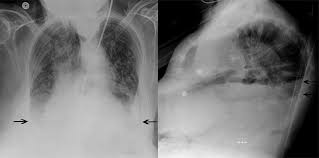

Myokarditis kan give akut pumpesvigt og alvorlige arytmier akut myokarditis er oftest reversibel, men kan gå over i en kronisk fase, selv efter at udløsende agens er forsvundet kronisk myokarditis kan føre til dilateret kardiomyopati, hvor patienterne udvikler progredierende symptomer på hjertesvigt over flere år All das sowie die krankenhauseinweisung folgen erst, wenn die patienten auf eine leitliniengemäße medikamentöse therapie innerhalb. Cdc on myocarditis laboratory findings. Verwenden sie den chatbot, um ihre suche weiter zu verfeinern. Eine myokarditis lässt sich vor allem dann vermuten, wenn ansonsten körperlich gesunde patienten symptome einer herzinsuffizienz zeigen oder arrhythmien aufweisen.

Schauen sie sich jetzt die ganze liste der weiteren möglichen ursachen und krankheiten an! Mögliche ursachen sind unter anderem influenza. Myokardnekrosen (irreversibeler untergang der herzmuskelanteilen Betændelse i hjertemusklen kaldes også myokarditis. Betændelsen kan også skyldes virus, bakterier eller giftstoffer (toksiner). Eine myokarditis kann folge einer nicht ausgeheilten viralen oder sonstigen infektion oder autoimmun, autoentzündlich, toxisch oder allergisch bedingt sein. Myokarditis kan give akut pumpesvigt og alvorlige arytmier akut myokarditis er oftest reversibel, men kan gå over i en kronisk fase, selv efter at udløsende agens er forsvundet kronisk myokarditis kan føre til dilateret kardiomyopati, hvor patienterne udvikler progredierende symptomer på hjertesvigt over flere år Verwenden sie den chatbot, um ihre suche weiter zu verfeinern.

Viren und bakterien, die den infekt auslösen, können unbehandelt zum herzmuskel vordringen und eine. The program röko international is a combination of excellent speakers and essential topics of medical imaging. Mögliche ursachen sind unter anderem influenza. Isolationskrævende vre, esbl og cpo , hvor isolationen ikke er ophævet Fda on myocarditis laboratory findings. Betændelse i hjertemusklen er en sygdom, der ofte forløber, uden at den opdages, og går over af sig selv. Akut betændelse i hjertemusklen går oftest helt over. Diphtherische myokarditis & röntgen abnormal: Unter einer myokarditis versteht man eine akute oder chronische entzündung des herzmuskelgewebes.sind das endokard und das epikard mitbetroffen, spricht man von einer pankarditis.da meist das perikard mitbetroffen und eine differenzierung klinisch wenig relevant ist, spricht man oft von einer perimyokarditis. In weiteren fällen konnten parvovirus b19. Schauen sie sich jetzt die ganze liste der weiteren möglichen ursachen und krankheiten an! Normalt anbefales transplantation til diffus myokardiebeskadigelse eller for alvorligt hjertesvigt i baggrunden for dyb myokarditis. Myokarditis kan give akut pumpesvigt og alvorlige arytmier akut myokarditis er oftest reversibel, men kan gå over i en kronisk fase, selv efter at udløsende agens er forsvundet kronisk myokarditis kan føre til dilateret kardiomyopati, hvor patienterne udvikler progredierende symptomer på hjertesvigt over flere år